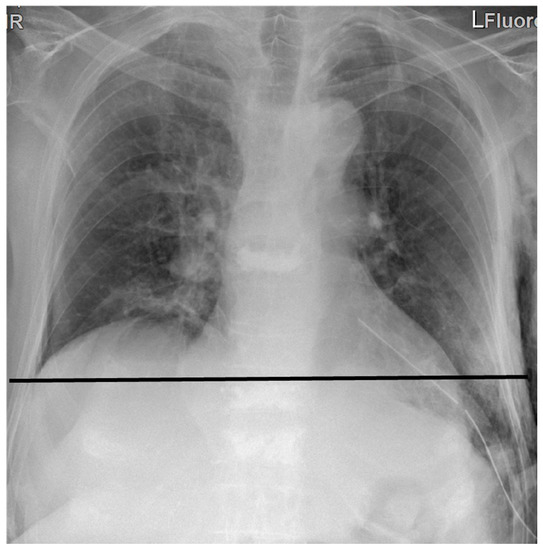

| Height of diaphragm om the X-ray (cm) | 8 ± 4 | 0.018 |

| Position of the plicated diaphragm on X-ray | 0.001 | ||

| Excellent (diaphragm reaches its original position) | 125 | 93 | |

| Satisfactory (2–3 cm higher than the original position) | 9 | 7 | |